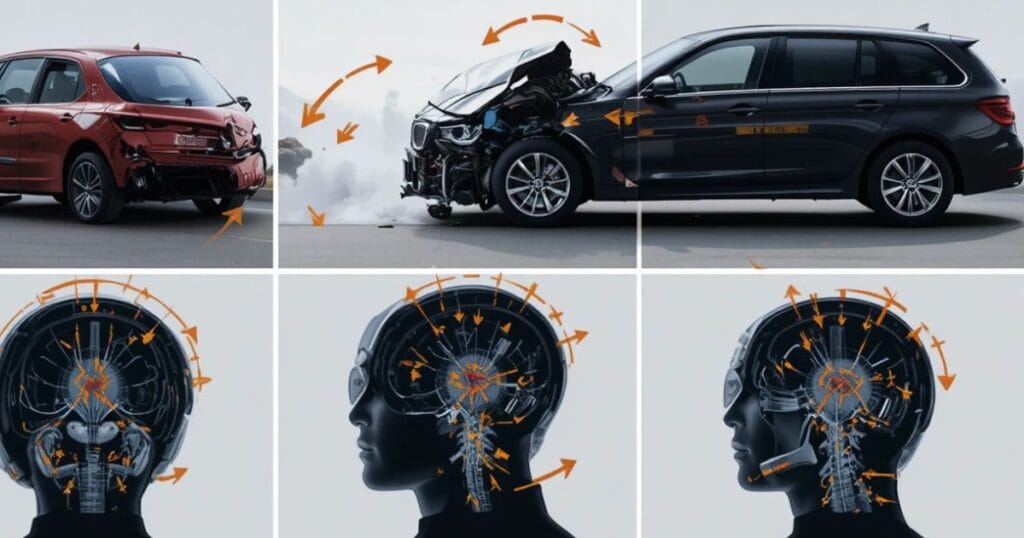

Common Causes of Head Trauma in Car Accidents

The force of a crash can violently shake the brain inside the skull, leading to a concussion, hemorrhage, or even brain swelling.

Some common causes include high-speed collisions, rear-end impacts, rollovers, and side crashes. Victims may also suffer a frontal lobe injury in accidents when the head strikes the dashboard or windshield. In many cases, these injuries aren’t visible immediately, making early neurological evaluation after crash vital.